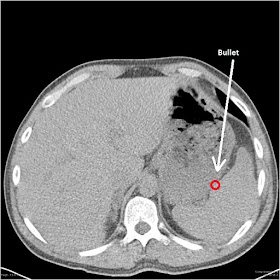

The bullet was overlying the left upper abdomen.

There are a lot of Very Important Structures between the right mid-back and the left upper abdomen, not the least of which are the right lung, heart, aorta and other great vessels, œsophagus, stomach, liver, duodenum, pancreas, spleen, and diaphragm. Holes in any of those things are by definition Very Bad Things, and holes in a few of them can be rapidly fatal, though obviously she shouldn't have any of those.

The problem is that an X-ray can't tell me if the bullet is in the soft tissue of the back (which would be fine), the soft tissue of the front (which would be much less fine, since it had to go through the entire body to get there), or somewhere in between (which would also be not at all fine), nor can it tell me what the bullet went through to get there. If the bullet was just in the soft tissue of the back, all she would need is a chest tube and no major abdominal or thoracic surgery. But you've already seen me foreshadow, so you know goddamned well that's not what happened.